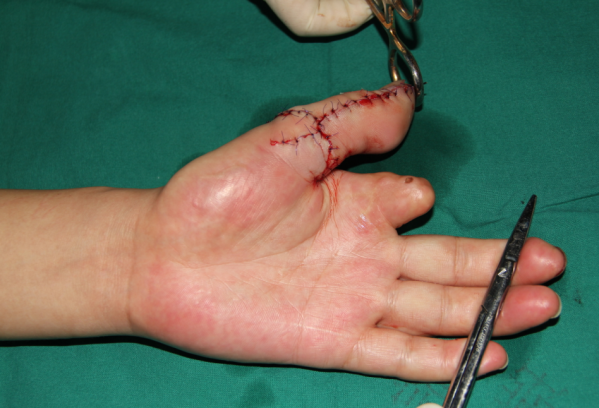

前天值班,来了7个再植的病人,初学者来省立医院进修是个很好的选择。这是其中一个。示指旋转撕脱,近侧指间关节处离断,保关节再植。

术前

非断面截骨

术后即刻,血管撕脱太厉害,动静脉还是移植了。